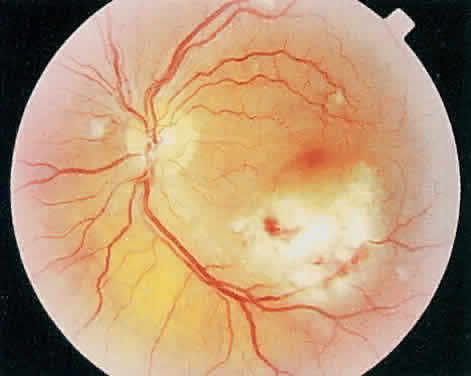

Over a course that usually spans weeks, infiltrates of CMV tend to assume two different patterns of clinical disease.11,12 The first pattern is called hemorrhagic and is characterized by broad geographic zones of retinal whitening. These large, geographic lesions are usually in close proximity to a major retinal blood vessel or the optic nerve. Satellite lesions are common. When the retinal necrosis associated with CMV retinitis becomes widespread, it is almost invariably associated with retinal hemorrhages. Although the border between necrotic and unaffected retina is sharply demarcated, the border itself appears irregular and jagged. Exudation into the retina or subretinal space may be seen, adding to the granular appearance of the retinitis. Juxtaposition of large zones of white, granular necrosis with those of red retinal hemorrhage has led this appearance of CMV retinitis to be described as either “pizza-pie” or “cheese and ketchup.” The retinal blood vessels, both arteries and veins, in the areas of necrosis commonly appear sheathed, secondary to a vasculitis. As a consequence, secondary retinal vascular occlusions, especially branch retinal vein obstructions, may occur in the course of CMV retinitis. Immune-mediated vascular damage may play a role in the vasculitis.12 Central healing of these lesions will occur as the infection progresses. Avasculitis resembling “frosted branch angiitis” hasbeen reported (Fig. 2).28 A second pattern of CMVretinitis has been labeled “granular” or “brushfireborder.” In this appearance, the focal granular infiltrates enlarge slowly across a line, leaving ever-increasing areas of destroyed retina and atrophic retinal pigment epithelium behind. Hemorrhages and vitreous cells are a less prominent feature. There appears to be direct cell-to-cell transfer of infected virions in this pattern of infection (Figs. 3 and 4). The brushfire border is commonly seen in CMV retinitis lesions anterior to the equator (Fig. 5). The significance, if any, of these two clinical patterns of CMV retinitis is not known, and, in some eyes, both patterns of disease can be seen simultaneously or in sequence. Progression of retinitis has been defined in clinical trials as movement of a lesion border at least 750 μm along a front that is 750 μm or more in length, development of a new CMV lesion in a previously involved eye or in the uninvolved fellow eye of a patient with baseline unilateral disease.29 Without treatment or improvement in the host's immune system, CMV retinitis is a relentless, slowly progressive infection resulting in blindness caused by total retinal necrosis, retinal detachment, or optic nerve involvement, in any combination.

CMV infection can affect the optic nerve either directly or by extension from adjacent retinitis (see Fig. 2).30–32 When direct involvement occurs, optic neuritis with profound, irreversible visual loss usually develops. Several cases of CMV optic neuritis associated with adjacent retinitis have been treated successfully. Exudative retinal detachment can occur during the course of CMV retinitis as well.4,12,30 The subretinal fluid is seen primarily inferiorly in the fundus and shifts with position. No retinal break will be evident; however, in areas of extremely thin, atrophic retina, it can be quite difficult to determine whether a full-thickness defect is present. Exudative retinal detachment associated with CMV is usually nonprogressive and may respond to ganciclovir therapy.